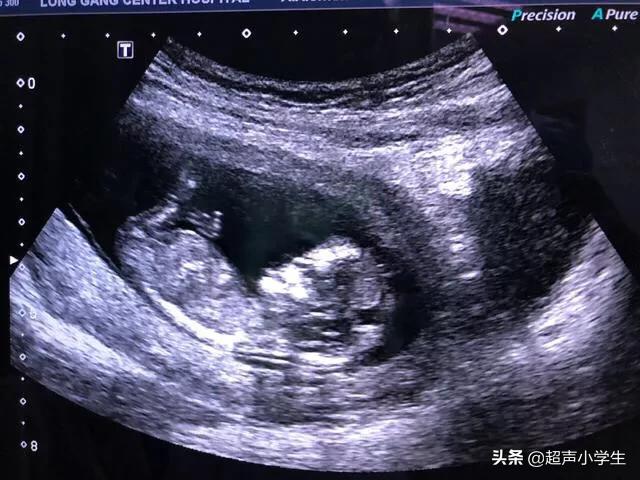

末次月经1月9号 但是月经一直不准确 2月27号b超未见胚芽回声 今天3月 号又做了b超 孕囊大小3 0 2 5cm胚芽回声约1 6cm 麻烦各位帮忙看看我现在怀孕几周了 妈妈帮问答